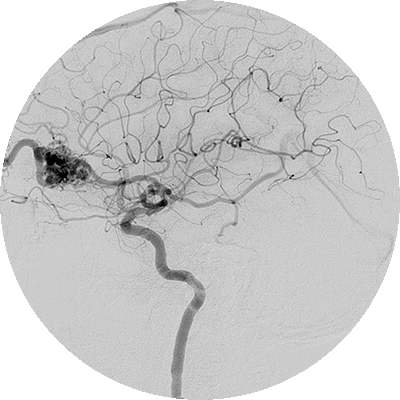

Ангиография

Диагностическая ангиография – это метод медицинской визуализации, используемый для визуального обследования внутренней полости, или просвета, кровеносных сосудов, в частности артерий, вен и камер сердца.

Основные области клинического применения ангиографии

- Диагностика обструктивных заболеваний сосудов

- Диагностика аневризм, в частности внутричерепных аневризм

- Диагностика артериовенозных мальформаций

- Диагностика кровоточащих сосудов

- Оценка наличия кровеносных сосудов в злокачественных опухолях

- Проведение вмешательств под визуальным контролем

Для проведения исследования в кровеносные сосуды вводится контрастное вещество и используются рентгеновские лучи. Аппараты, используемые для ангиографии, могут быть обычными и цифровыми. Наиболее широко используется цифровая субтракционная ангиография.